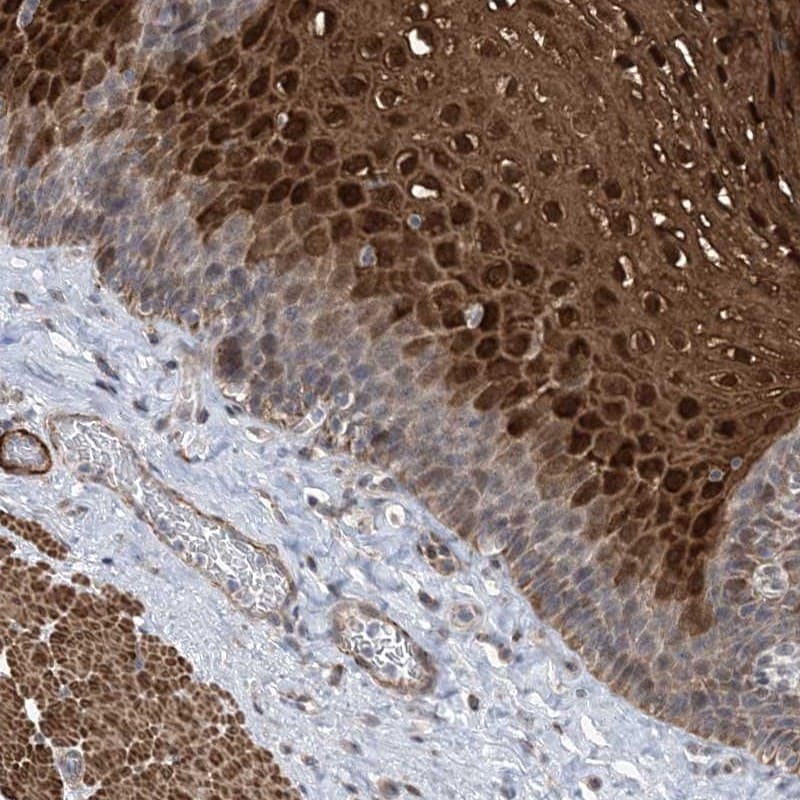

- Immunohistochemical analysis of ZNF8 in human esophagus using ZNF8 Polyclonal Antibody (Product # PA5-57061) shows strong nuclear and cytoplasmic positivity in superficial cells of squamous epithelia.